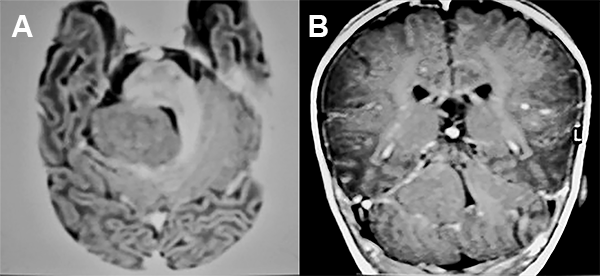

Paciente de 4 años de edad sin antecedentes perinatológicos de importancia que a los 3 años de edad comienza con movimientos clónicos de comisura labial a derecha que fueron asumidos como normales. Ocho meses después del inicio de los movimientos clónicas de la comisura labial, la niña presenta fijeza de la mirada con posterior desviación de la comisura labial a derecha y posteriores movimientos tónicos clónicos generalizados que se repitieron varias veces (fig. 7).

Figura 7: Caso 4: Imágenes preoperatorias